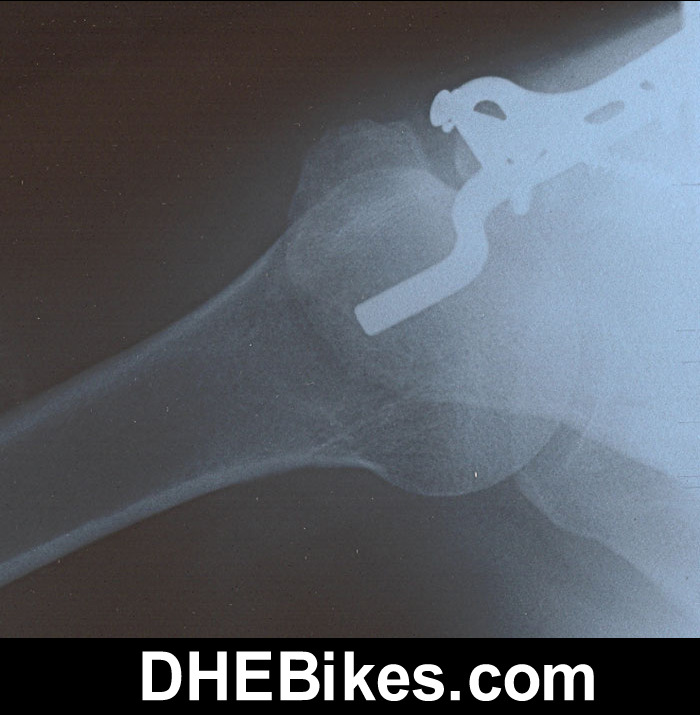

This is the pre-surgery x-ray of Downhill Dave's right shoulder. They should have operated at the hospital at the time of the accident but for some reason did not. 5 months after the accident the bones were still almost 2cm apart and would never fuse so surgery was required.

This crash happened during bike testing of a new all mountain bike from the Czech Republic where I was doing urban freeriding in Downtown Vancouver trying to break the dual suspension frame (to test its limits before I began distributing it). Unfortunately I did not know that the manufacturer had put light duty cross-country tubes in and when I landed about a 6 foot concrete staircase jump to flat the front tiire blew immediately, wrapped around the fork and slammed me into the concrete. OOOPSSS!!!

This is the after-surgery x-ray of Downhill Dave's right shoulder.

The titanium hardware consists of 6 bolts/ screws and the one big plate.

About a year after the surgery, I actually had to have another surgery to remove the titanium as it was binding in my shoulder and causing extreme pain.